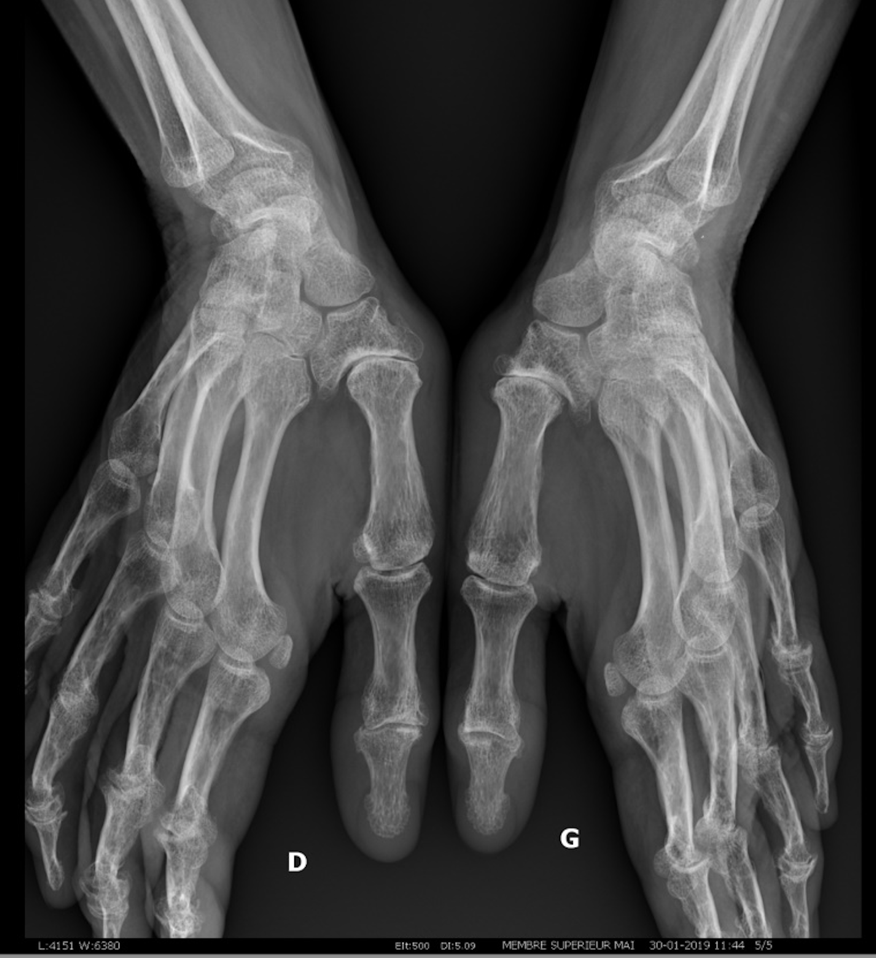

Le diagnostic repose sur des radiographies

- Figure 1 rhizarthrose et arthrose des doigts longs

- Figure 2 rhizarthrose bilatérale